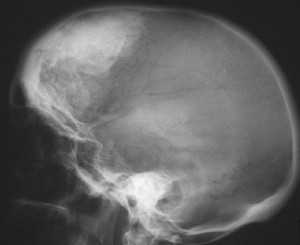

Диагноз ставят на основе жалоб и клинической картины; также используют гистологические методы исследования. На рентгенограмме визуализируется утолщение лобной кости. Синдром Морганьи — Стюарта — Мореля дифференцируют в первую очередь от болезни Иценко — Кушинга и адипозогенитальной дистрофии.

Основным проявлением синдрома М.С.М., без которого он не существует как таковой, является утолщение внутренней пластинки лобной кости (гиперостоз). Это своеобразное разрастание гиперплазированной костной ткани, хорошо распознаваемое рентгенологически и не определяемое при осмотре и пальпации. Явление это довольно распространенное, но в большинстве случаев не проявляется клинически и является рентгенологической находкой [18, 34, 35].

Рентгенологически определяются костные разрастания на поверхности внутренней пластинки лобной кости; они могут быть довольно ограниченными или занимать обширные участки. Иногда они диффузно распространяются на свод черепа, реже - на его основание.

Рентгенограмма черепа (боковая проекция) больного с синдромом Морганьи: резкое утолщение лобной кости (указано стрелкой) за счет гиперостоза внутренней пластинки.

Диагноз устанавливают на основании клин, картины и данных ЭЭГ. Для уточнения диагноза необходимо рентгенол, исследование, т. к. гиперостоз внутренней пластинки лобной кости (рис.), являющийся обязательным признаком этого синдрома, может быть выявлен только при краниографии (см.). О локализации и протяженности изменений судят по снимкам черепа в боковой проекции. Как правило, дополнительные костные разрастания в виде отдельных узлов или разлитого характера располагаются в средней и нижней третях чешуи лобной кости, изредка — и в теменных костях. По сравнению с неизмененными участками кость может быть утолщена в 2—3 раза. Этим изменениям могут сопутствовать различной формы и размеров очаги обызвествления твердой мозговой оболочки в зоне, примыкающей к внутренней поверхности лобной кости.

При длительном течении заболевания и резко выраженном гиперостозе лобной кости из-за уменьшения объема черепа на краниограммах могут быть обнаружены признаки повышения внутричерепного давления (усиление пальцевых вдавлений, углубление борозд синусов и др.).